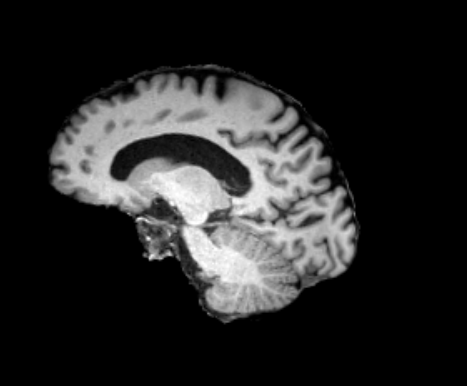

3.2.2 Robustness

In this experiment, we evaluate the robustness of Polaffini and the competing methods by computing a failure rate. We considered as potential outliers all cases for which the average Dice score over all regions after registration was below 0.34 (Z-score below -1.5, pooling Dices from all affine methods). All potential outliers were visually inspected to assess the reason behind the poor anatomical structure overlap score. All of them were clear failure cases, not just a residual misalignment to be expected after an affine registration. The failure counts for each method are reported in table 2. Almost all of the failure cases only occurred when registering with Flirt, mostly when subjects from the IXI dataset were involved. The most common failure type, showcased in Fig 6-a., consists of a local minimum where the frontal part of the moving brain is matched with the cerebellum of the reference one, a less frequent upside-down outcome is showcased in Fig 6-b. We suspect it is due to the fact that images from IXI have their axes ordered differently compared to the other two datasets and the template. However, since this information is contained in the header, it is unclear why Flirt could not handle the situation properly. Without the restriction of the angle search to , Flirt would give worse results (19 failure cases for subject-to-template and 61 for subject-to-subject). The only failure case using Anima for subject-to-subject is shown in Fig 6-c. For the rest of this section, we discard registrations if at least one of the methods has failed.

| reference | moving | moved | reference and moved | |

| a. | ukb_1154012-20252 | adni_AD-012-S-0720 | registered with Flirt | |

![]() |

|

| b. | ixi_165-HH-1589 | ukb_1145033-20252 | registered with Flirt | |

| c. | ixi_143-Guys-0785 | adni_MCI-003-S-6258 | registered with Anima-aff | |